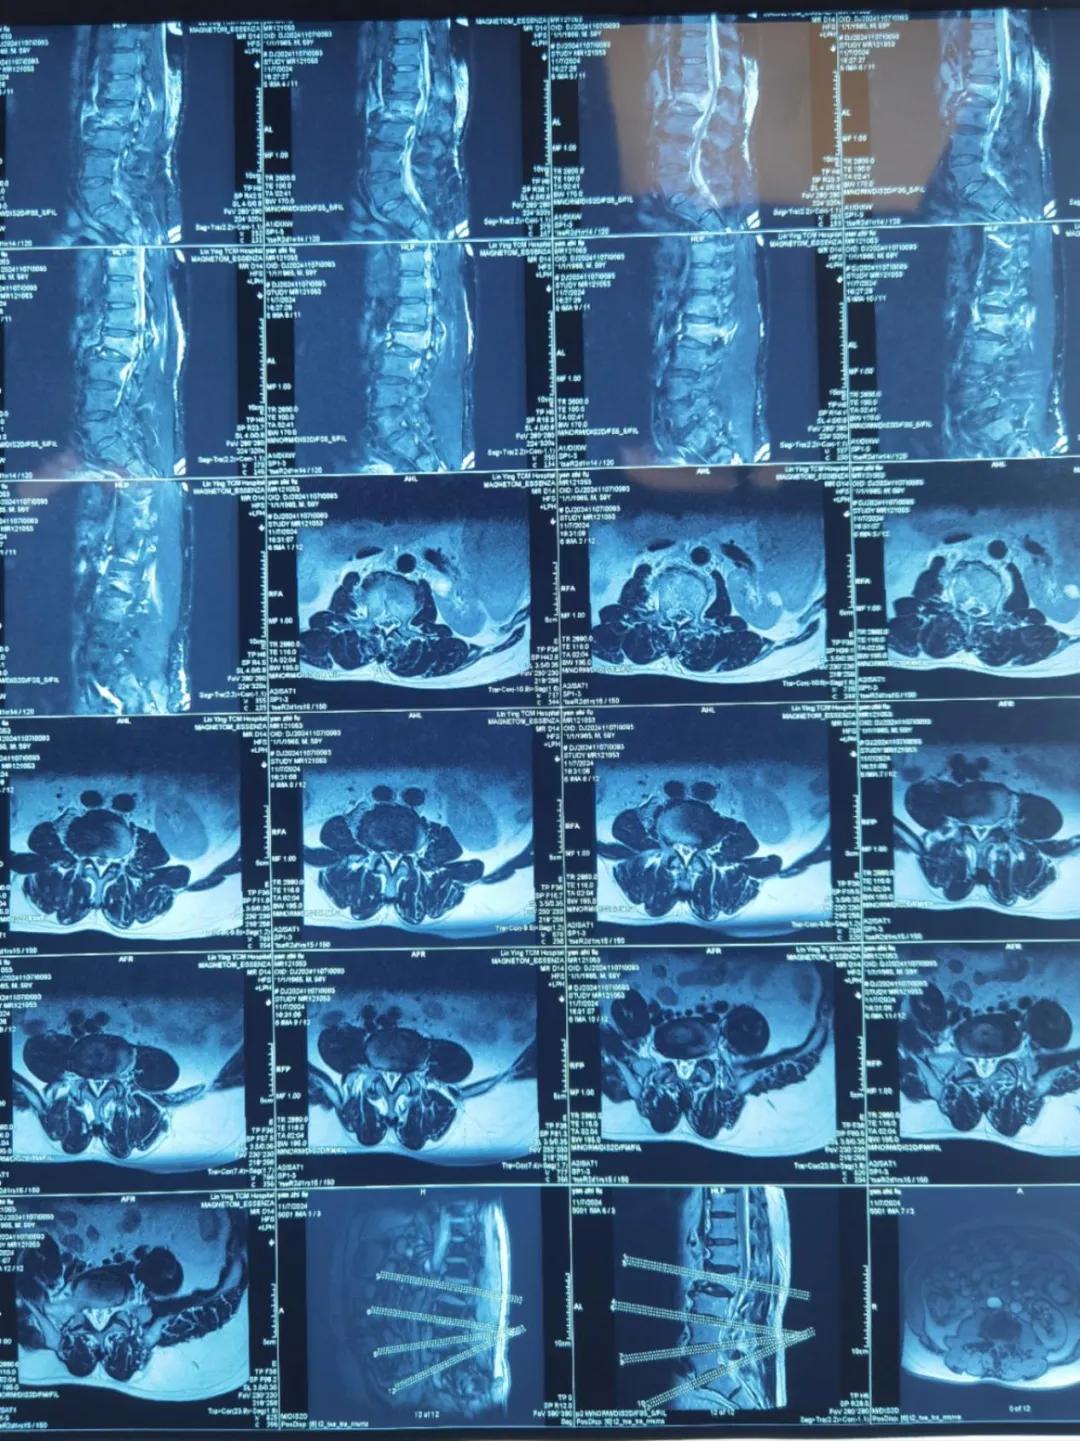

“醫(yī)生,這是之前的檢查結(jié)果,還需要再做檢查嗎?”閆大叔從外院轉(zhuǎn)來被推進智能微創(chuàng)骨科。幾天前,他在老家的中醫(yī)院進行了抽血檢驗和磁共振檢查,因為腰疼嚴重、行動不便檢查過程也十分不易。

智能微創(chuàng)骨科副主任李鵬認真檢查了閆大叔帶來的片子,還有電腦系統(tǒng)上彈出來的檢驗結(jié)果。外院的核磁和X線可以清楚的看到情況已經(jīng)比較嚴重,需要盡快手術(shù)。沒有二次檢查,不僅節(jié)省患者就醫(yī)費用,還使就醫(yī)更高效、便捷直接入院接受治療。閆大叔懸著的心放了下來,其他醫(yī)院的片子能直接用,檢查在家附近的醫(yī)院做,手術(shù)在漯河市骨科醫(yī)院做,便捷的結(jié)果'互認'讓他直夸“真方便!咱老百姓更省心、更放心了!”